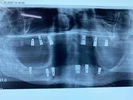

Implant Treatment